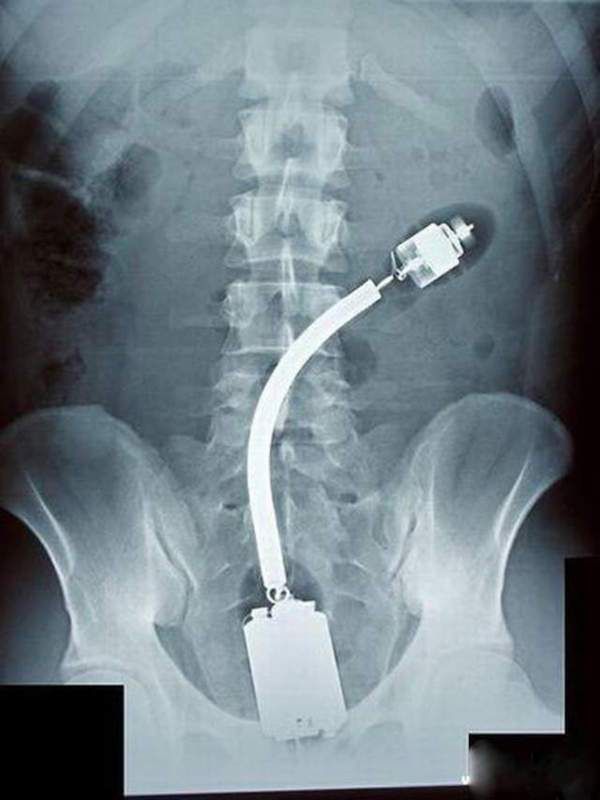

/ 15Nawet lekarze byli zdumieni

Obraz

© imgur.com

Co to jest i jak się tam dostało?!